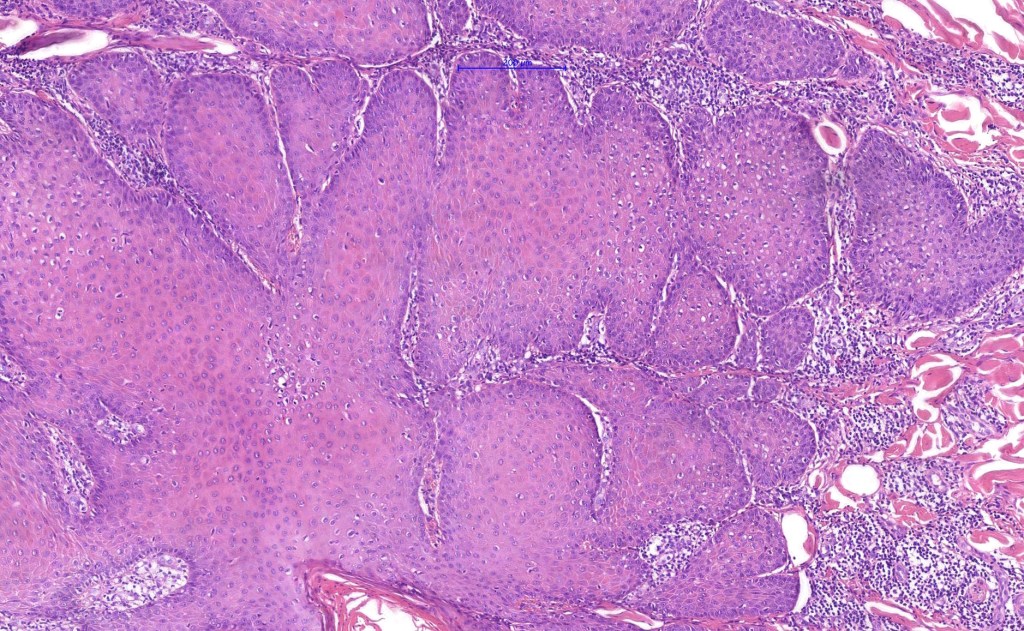

Histological features

•Multilobulated cyst with associated lobules of well differentiated squamous epithelium

•PAS+ve cytoplasmic vacuolation indicating outer root sheath differentiation

•+/- peripheral palisading

•No pleomorphism or significant mitotic activity

•Eosinophilic basement membrane

•Infundibular>trichilemmal keratinization